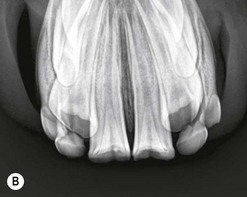

image image

Fig. 13.24 Intra-oral radiographs of the mandibular incisors of: (A) a yearling with a fractured mandible (note the obliquity of the left incisors compared to the right). The developing buds of the permanent 301 and 401 can be seen mesial to the 701 and 801. (B) A 3-year-old horse. The 301 and 401 (central incisors) are erupted but the deciduous lower 02s and 03s remain in wear. Note the canines are superimposed on the developing permanent 03s.